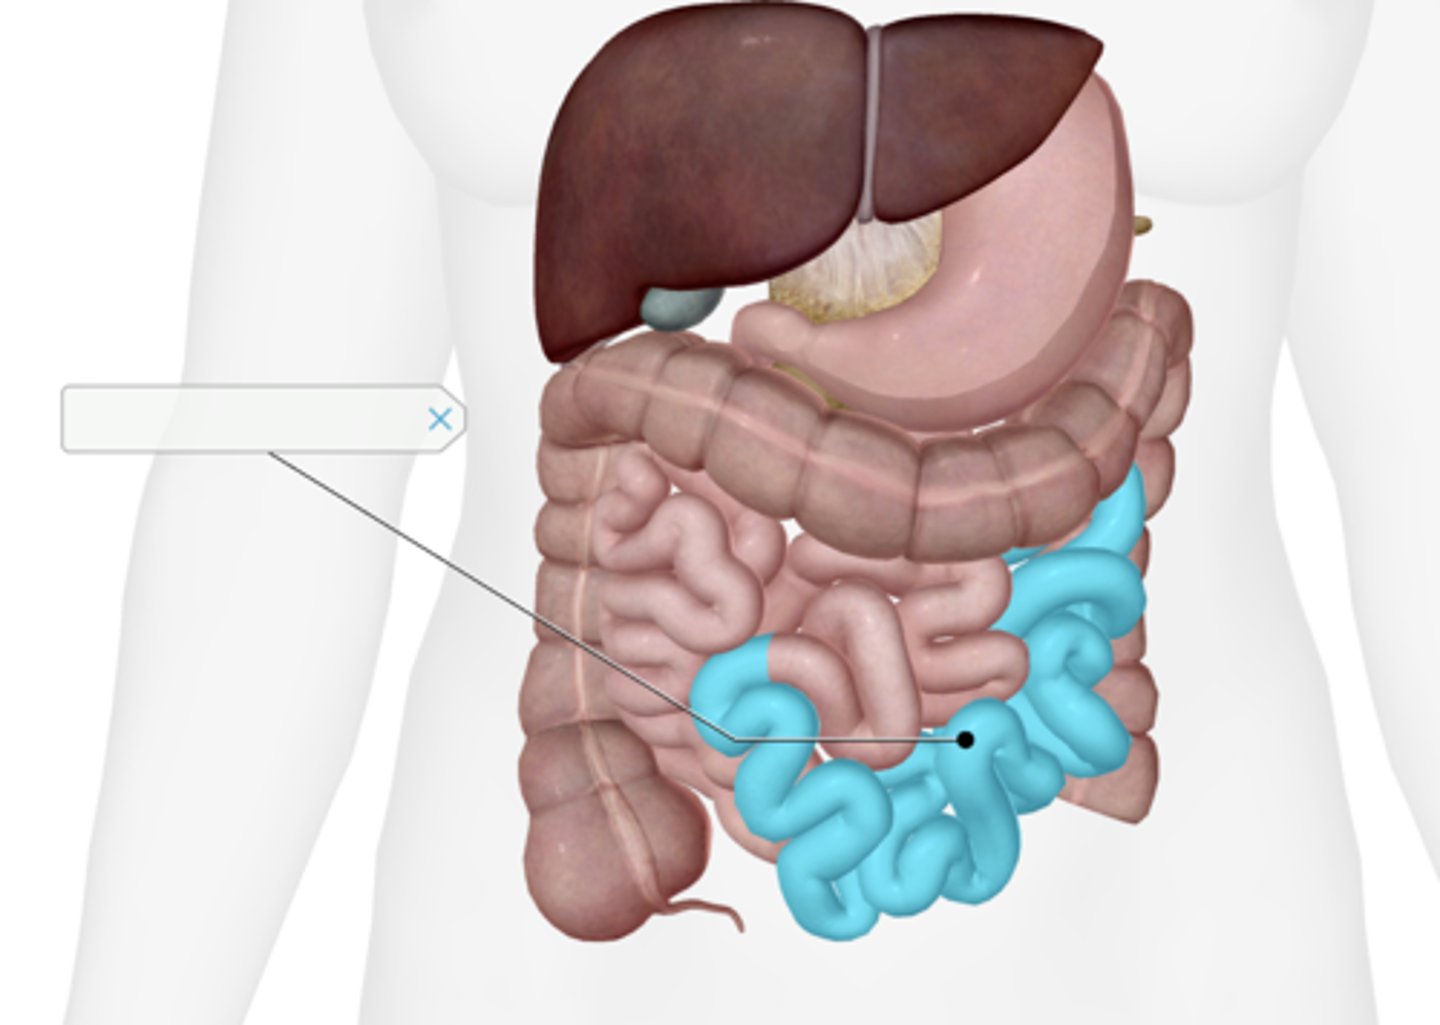

Jejunum

Ileum

Taenia coli

(only partially selected)

Superior mesenteric artery

Inferior mesenteric artery

Cecum

Appendix

Ascending colon

Transverse colon

Descending colon

Sigmoid colon